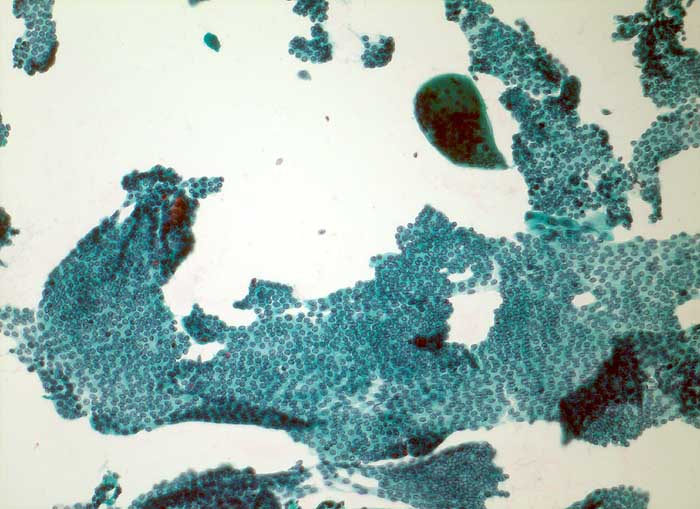

papilläres Schilddrüsenkarzinom

Schilddrüse Feinnadelpunktion: Die Tumorzellen bilden flächenhafte wohlgeordnete Verbände. Sehr wenig Kolloid. Eindeutige papilläre Strukturen fehlen. Riesenzelle.

Mehrkernige Riesenzellen in der FNP der Schilddrüse:

- subakute Thyreoiditis de Quervain oder Hashimoto Thyreoiditis

- papilläres Karzinom

- Granulationsgewebe, postoperativ

- mediane Halszyste

- Zyste (mehrkernige Schaumzellen)

- anaplastisches Karzinom mit osteoklastenartigen Riesenzellen

- medulläres Karzinom oder Glomustumor (selten)